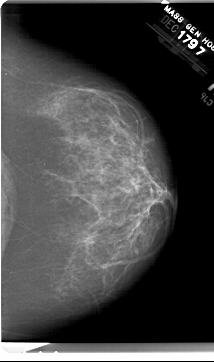

A_1518_1.RIGHT_MLO

LEFT_MLO LINES 6601 PIXELS_PER_LINE 4441 BITS_PER_PIXEL 12 RESOLUTION 43.5 OVERLAY